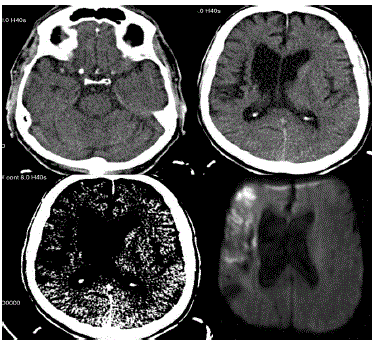

Paciente LSM, masculino, com 62 anos é admitido na emergência com um quadro semelhante ao de um insulto vascular e com início há três horas. A acompanhante trouxe exame anterior que demonstrava sequela de insulto vascular isquêmico na ínsula com extensão a coroa radiada à direita.

As imagens realizadas no momento da admissão estão a sua disposição.

Baseado nas imagens disponibilizadas, qual o seu diagnóstico?